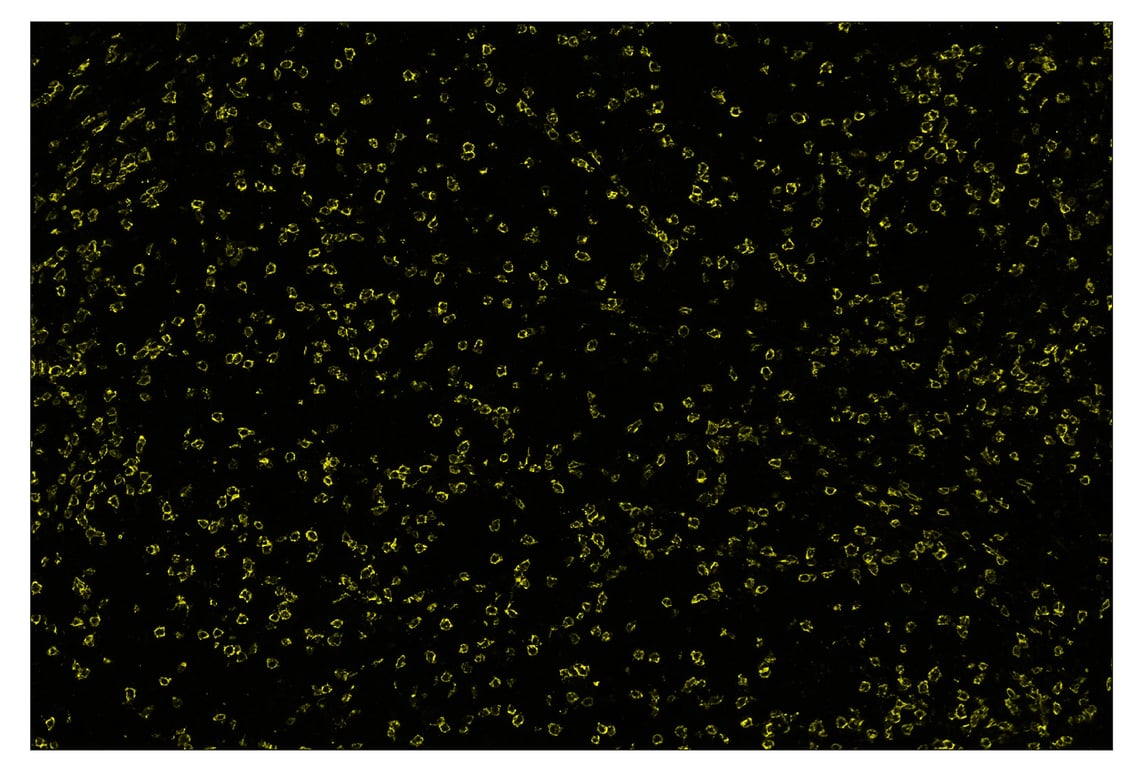

Immunohistochemistry Image 2: CD8 alpha (D8A8Y) & CO-0004-594 SignalStar<sup>™</sup> Oligo-Antibody Pair

SignalStar™ immunohistochemical analysis of paraffin-embedded human gastric adenocarcinoma using CD8α (D8A8Y) & CO-0004-594 SignalStar™ Oligo-Antibody Pair #19166 (yellow). All fluorophores have been assigned a pseudocolor, as indicated. Staining was performed on the BOND RX by Leica Biosystems.